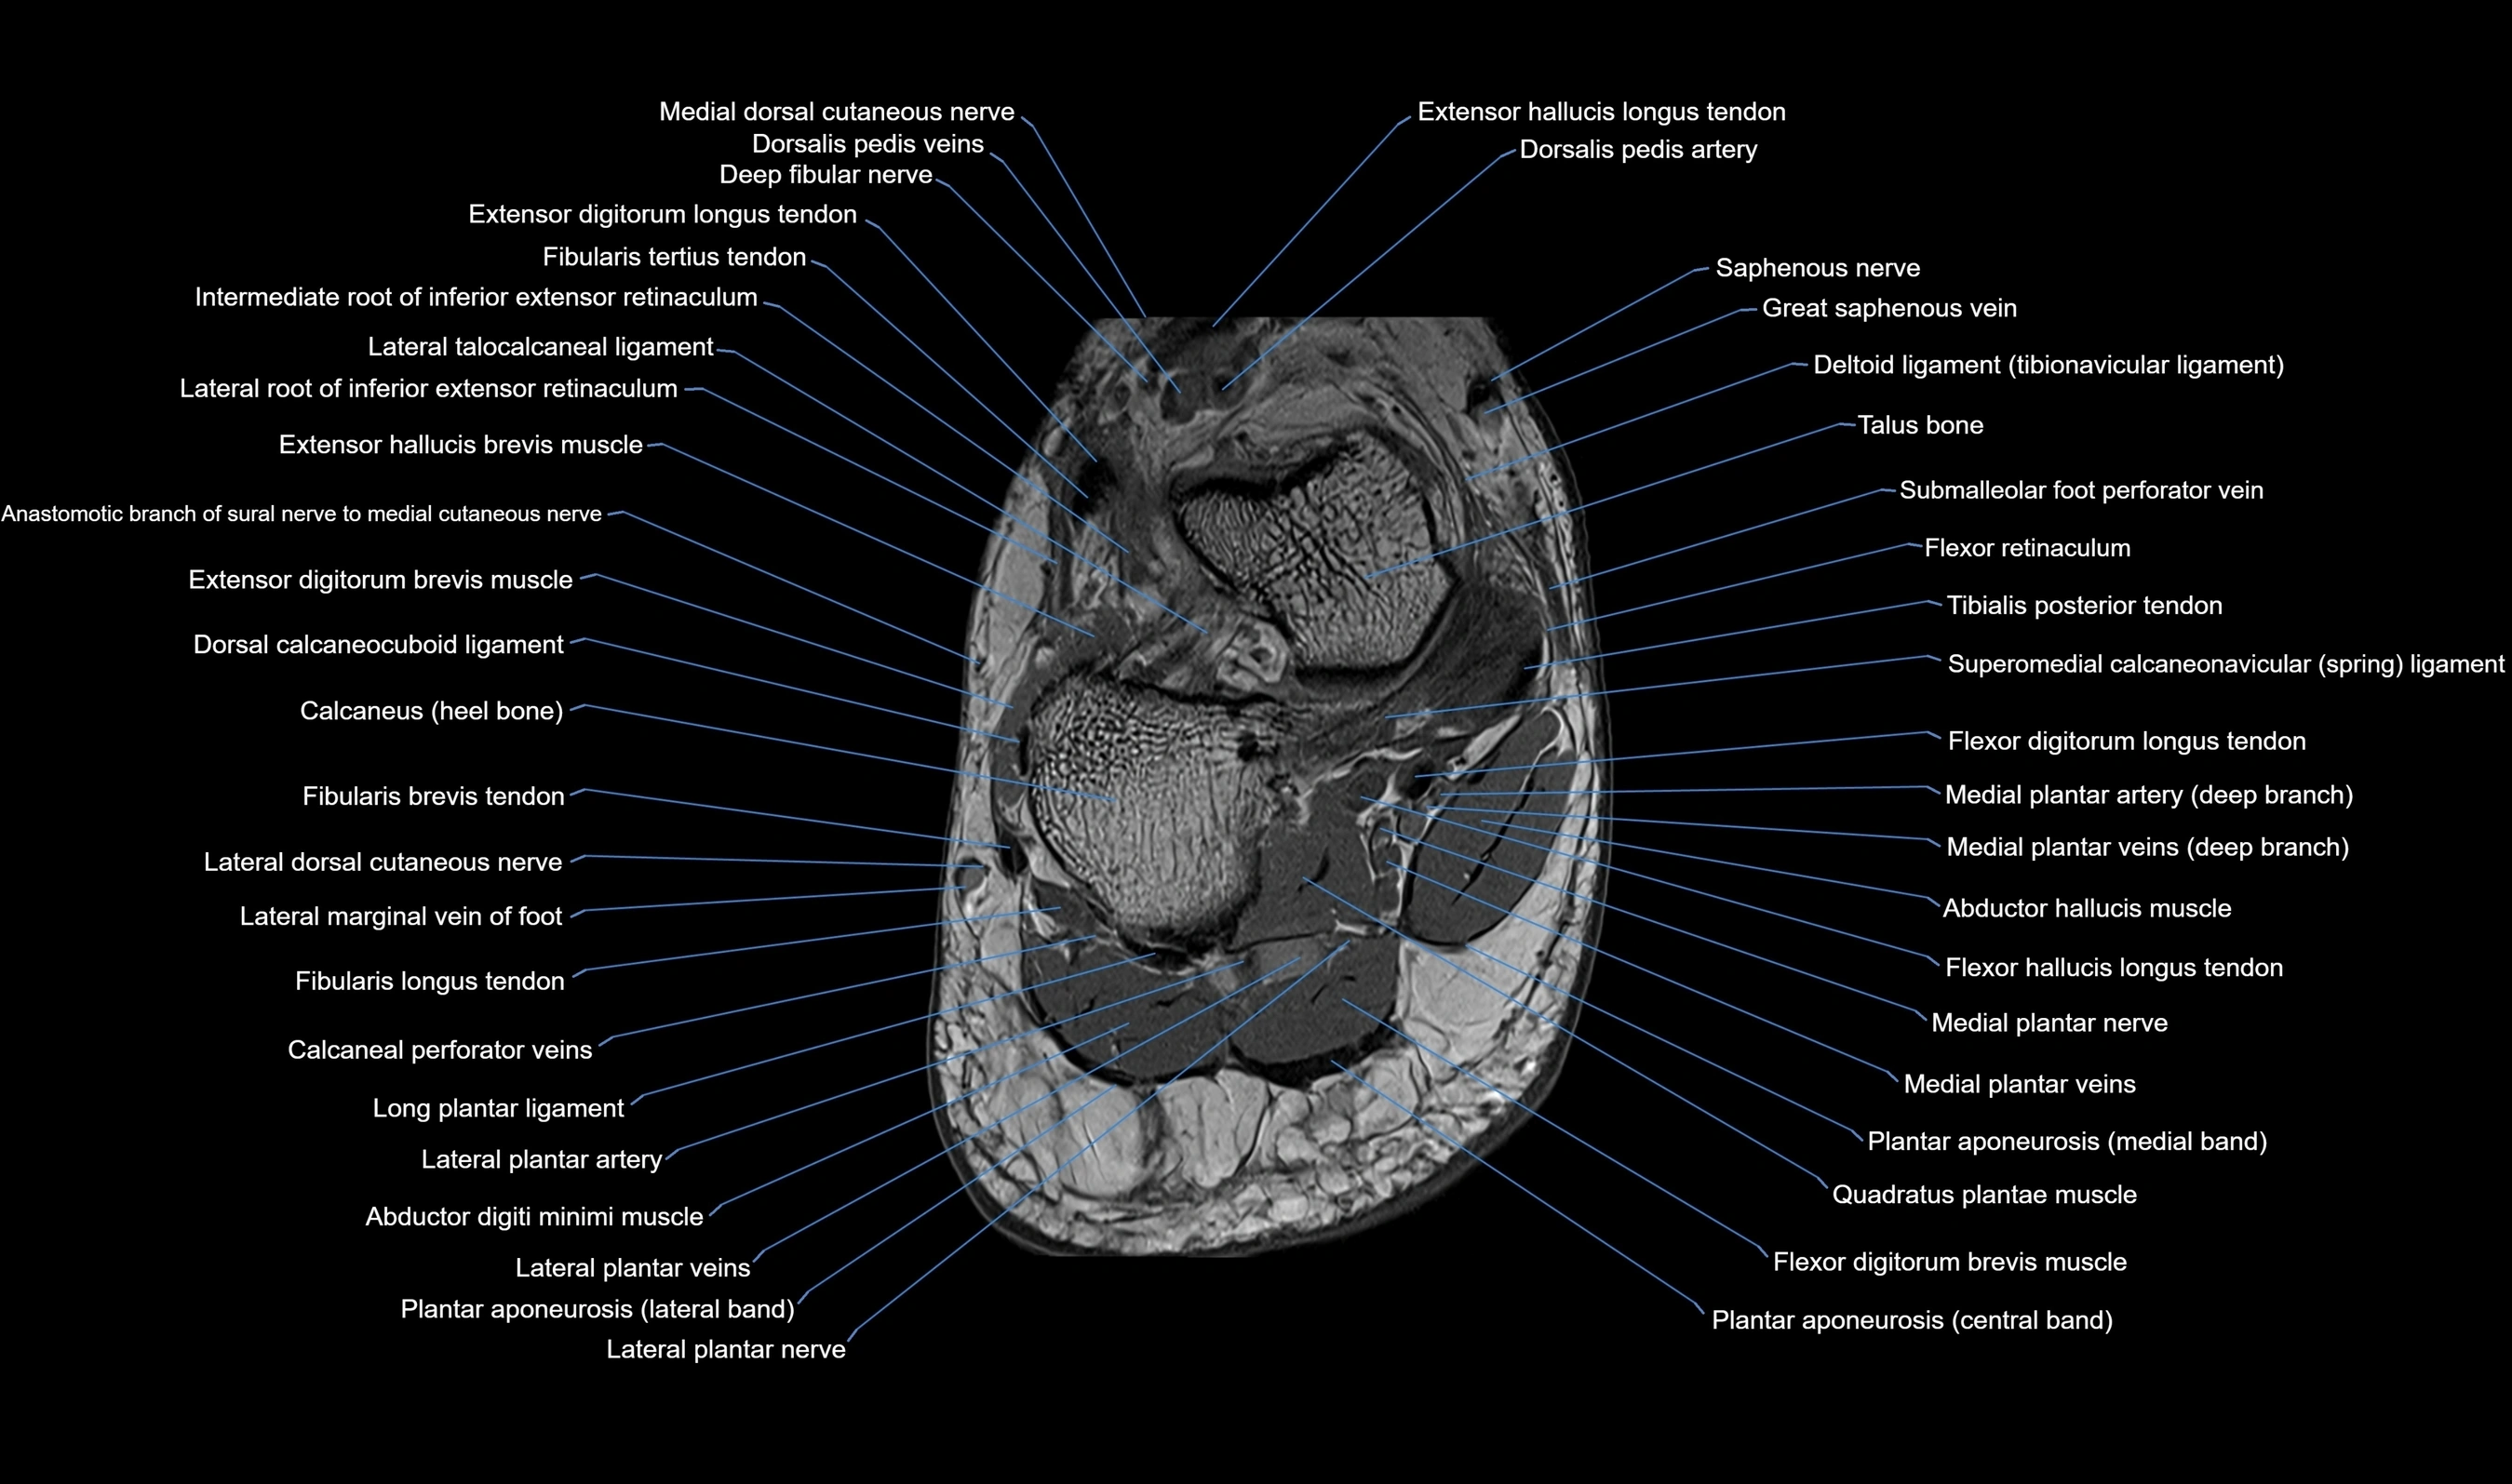

MRI image